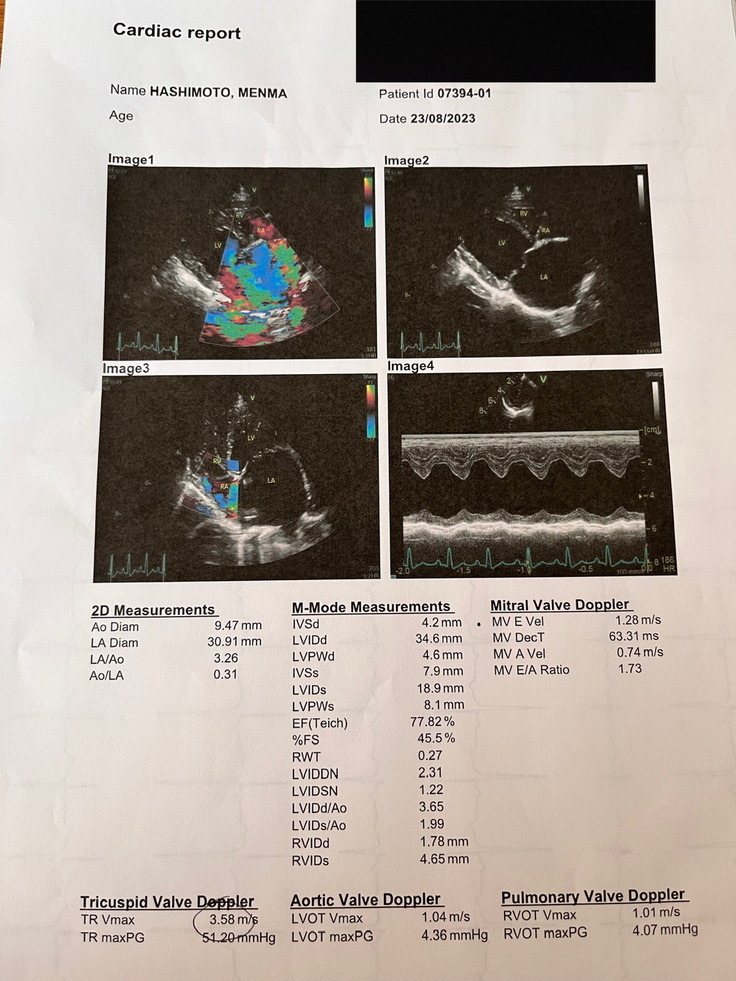

(↑この時撮っていただいた心臓の画像)

さらに、詳しく検査をした結果、めんまは僧帽弁閉鎖不全症ステージCであること、そしていくつもの併発症があることが発覚しました。

(↑診断書 ※ペット保険に加入しているのが夫なので、保険金申請の時に便利だろうということで飼い主の氏名が夫のものになっています)

(↑動物病院の資料)